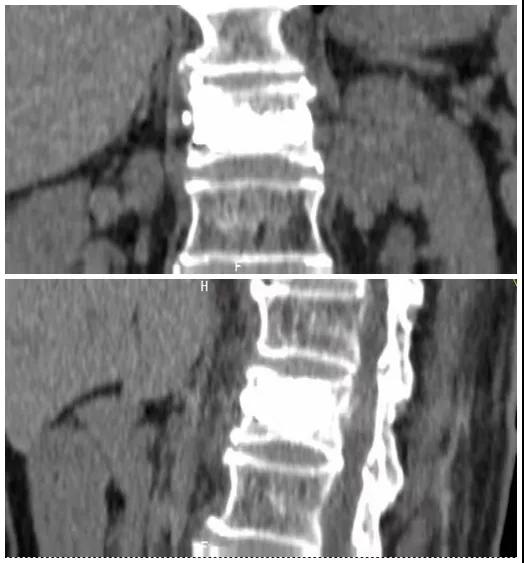

術(shù)前磁共振檢查提示腰1椎體新鮮壓縮性骨折

術(shù)后復(fù)查CT可見(jiàn)骨水泥彌散充分

經(jīng)術(shù)前分析詳細(xì)評(píng)估,由骨科副主任張宏宇及科室團(tuán)隊(duì)順利為患者進(jìn)行了經(jīng)皮穿刺椎體成形術(shù),術(shù)后患者疼痛明顯減輕。同時(shí),科室團(tuán)隊(duì)還為她制定了科學(xué)的抗骨質(zhì)疏松治療,目前患者已康復(fù)出院。